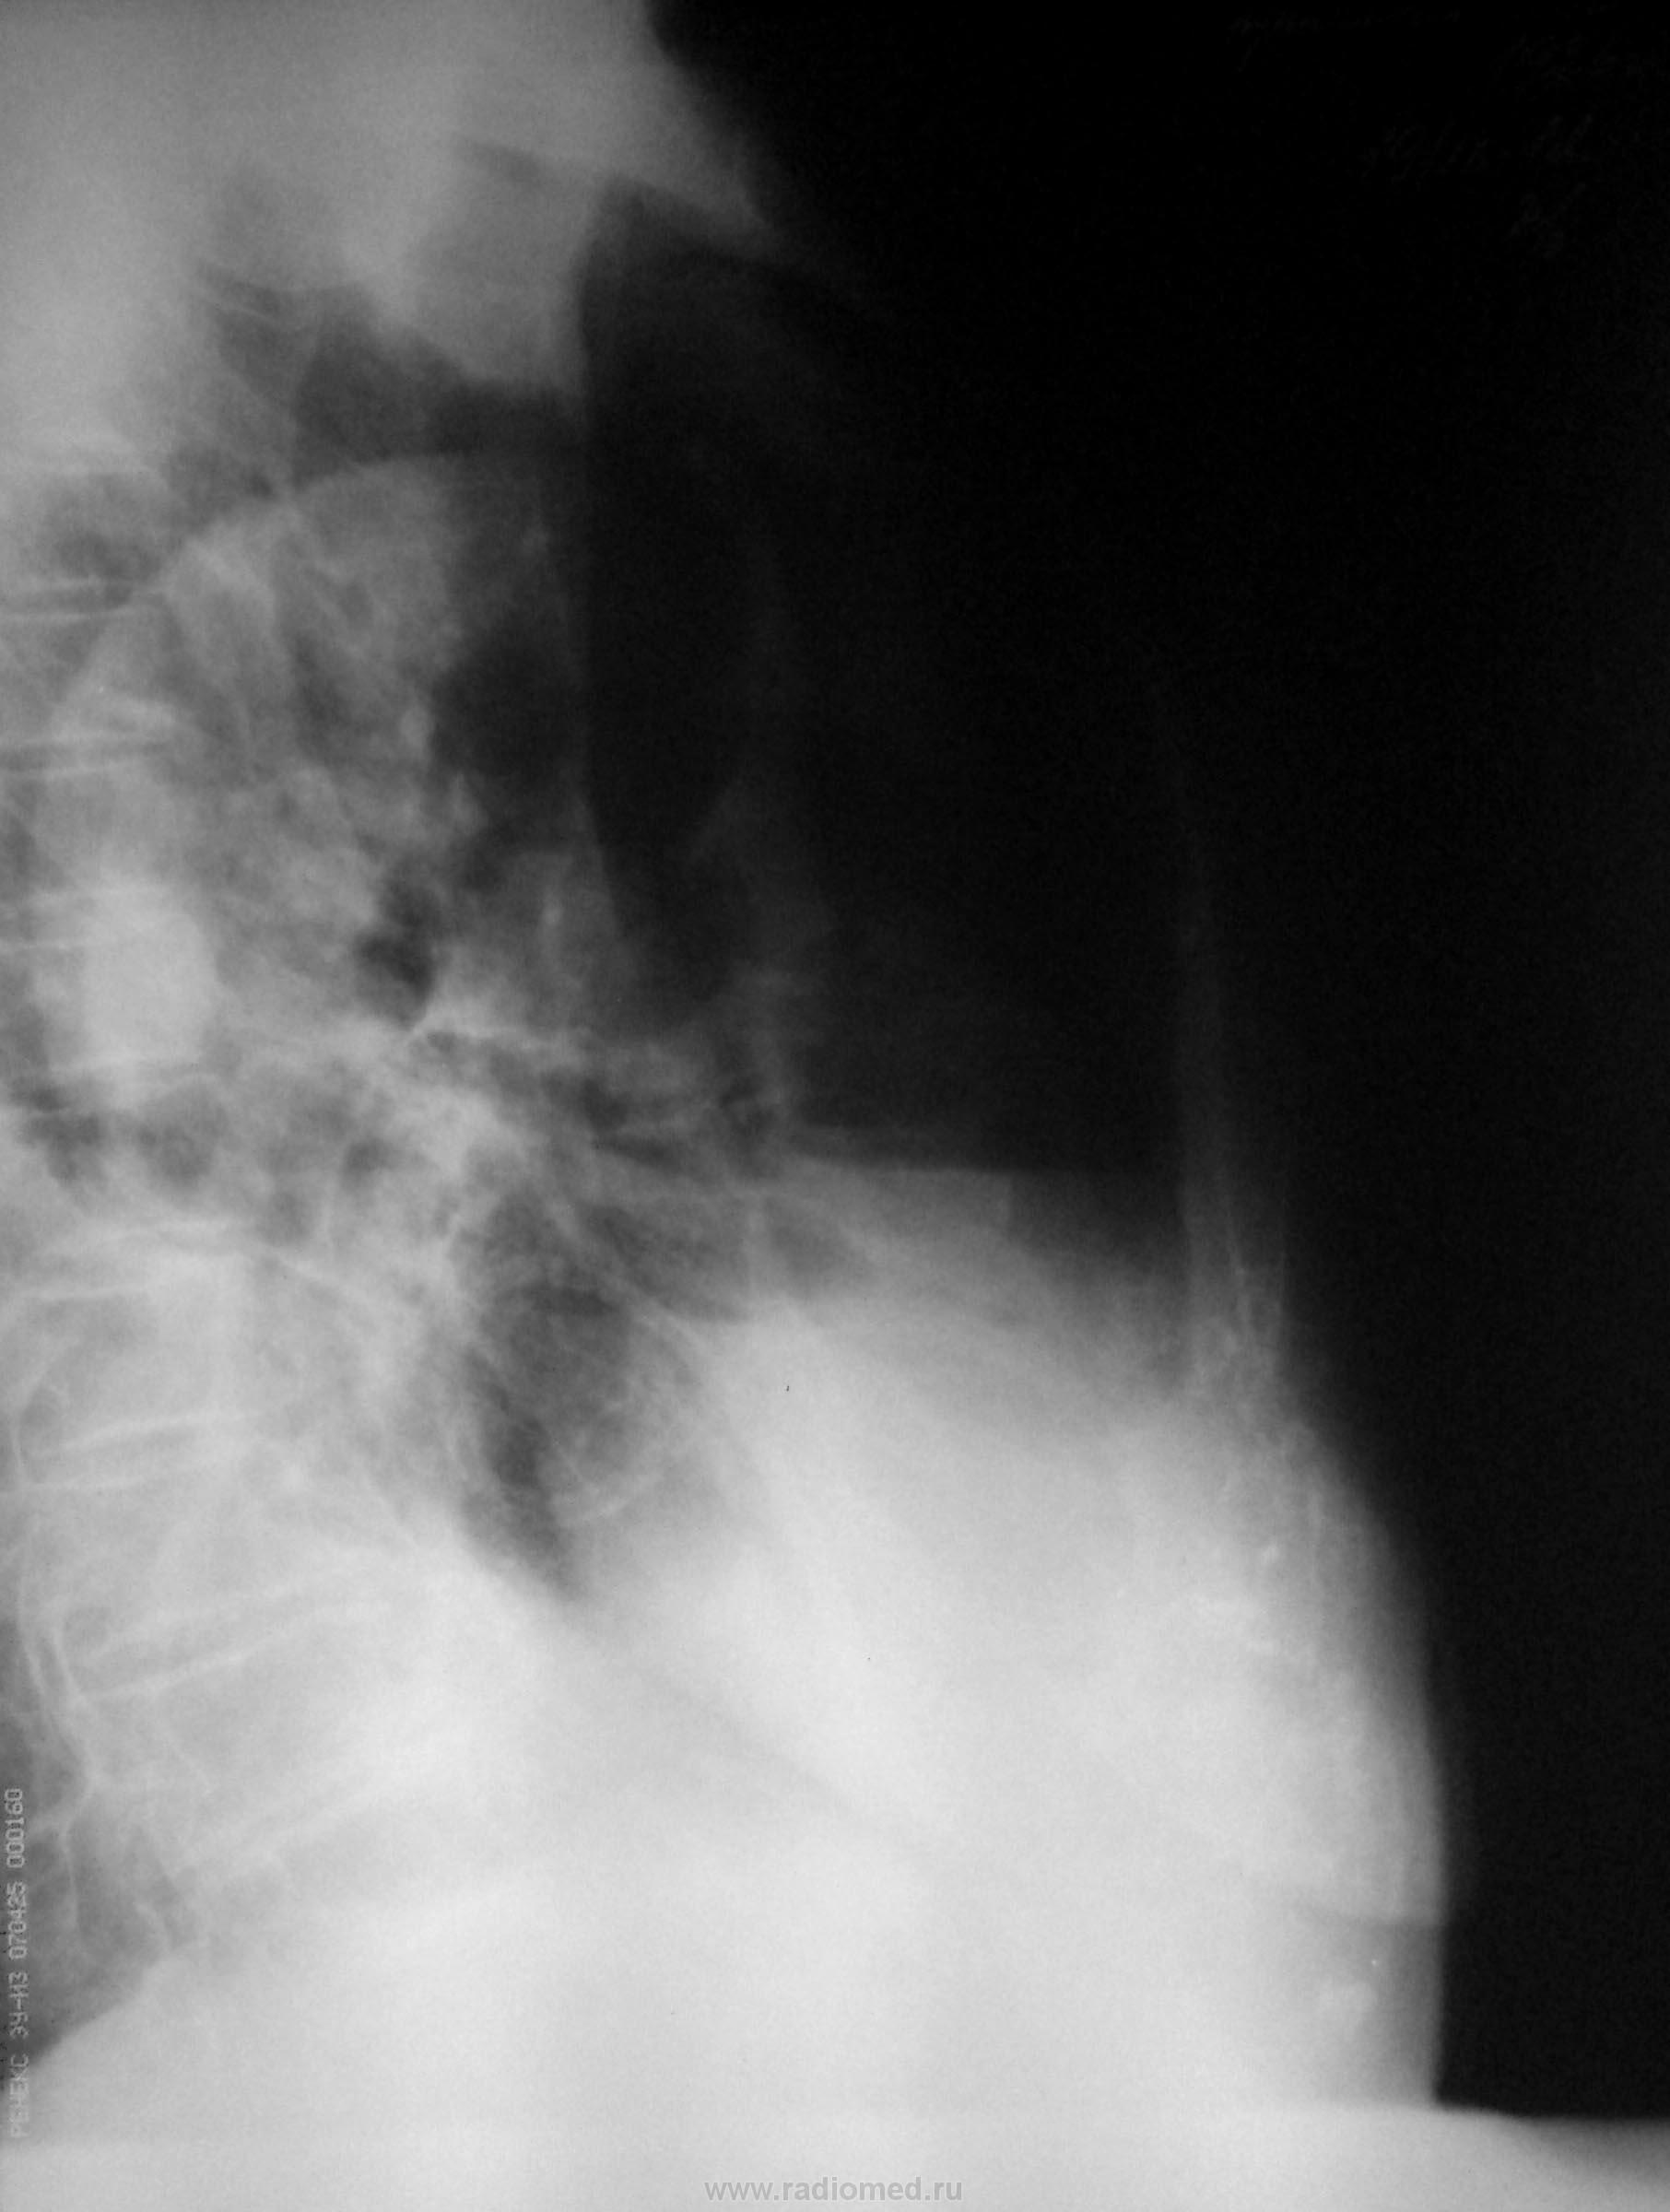

На рентгенограмме признаки гидроторакса справа, проведена плевральная пункция, установлен дренаж. Получено 2000 мл серозно-геморрагической жидкости.

После плевральной пункции проведено контрольное рентгенологическое обследование.

Не могу разобраться, что за уровни жидкости на рентгенограммах при контрольном исследовании, возможно жидкость между плевральными спайками? Какова природа гидроторакса? Очень интересно ваше мнение…

1. при поступлении

2. после пункции

3. правый бок

Развитие пневмогидроторакса после плевральной пункции, на фоне спаечного процесса?